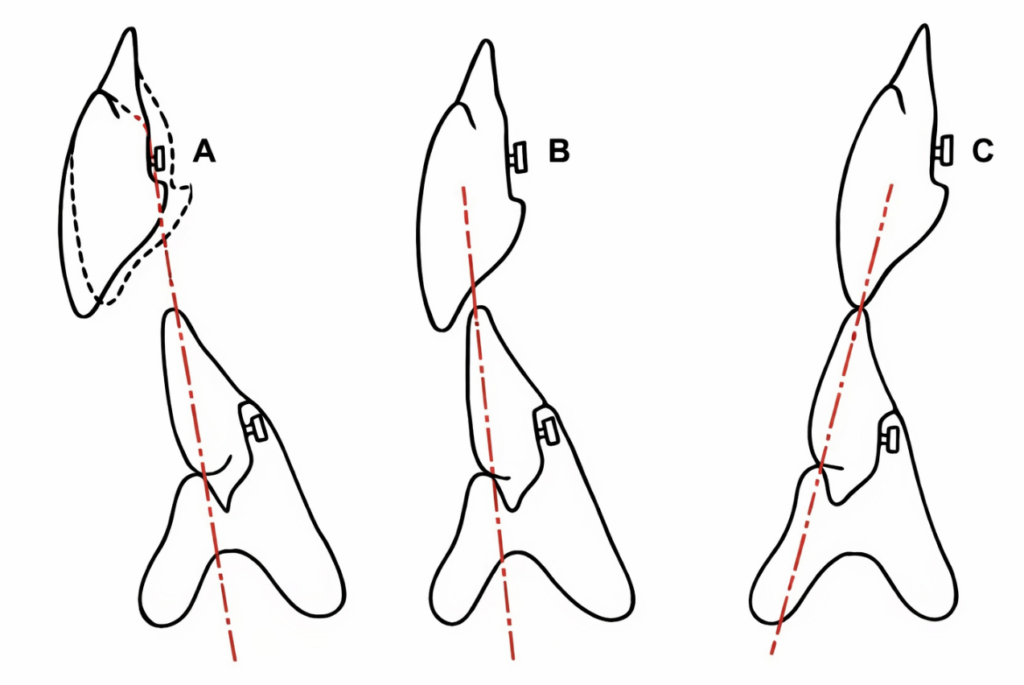

Cas particuliers de montage

- Devant une rétrognathie mandibulaire (classe II d’Angle) : les impératifs du montage restent les mêmes, seul l’overjet sera accentué.

- Si on a une prognathie inférieure (classe III d’Angle) : le montage antérieur se fera en bout à bout.